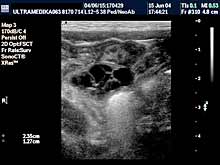

- Testisi

Pregled testisa, bez obzira da li postoji bol ili sumnja na

zapaljenje su apsolutna indikacija za pregled. Ultrazvučna

dijagnostika testisa može otkriti i zloćudni tumor testisa kod

mladih ljudi kod kojih su testisi normalnih karakteristika nakon

kliničkog pregleda pipanjem od strane lekara. Ultrazvučna rana

dijagnostika je osnovni preduslov za uspešno lečenje. Otkrivanje

proširenih vena testisa i nakon toga hirurška intervencija

sprečavaju pojavu smanjene proizvodnje spermatozoida.